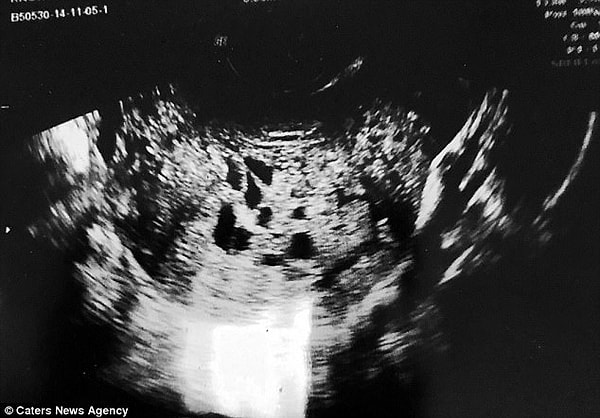

Однако на 7 недели беременности у Лорен началось обильное кровотечение, и она решила сходить на УЗИ.

3. После проведенного ультразвукового исследования, врачи сказали Ноулз, что у нее молярная беременность — в ее утробе развивается не ребенок, а раковая опухоль.